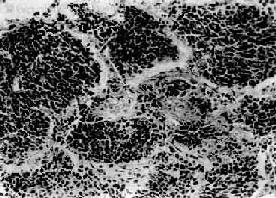

(2)小细胞:发生率在肺中居第二位(临床统计在40%以上,尸检统计占15%~25%)。患者男多于女(20:1),发病年龄约在35~60岁。小细胞肺亦多发生于肺中央部,生长迅速,转移较早,恶生度高,5年存活率仅1%~2%。小细胞细胞很小,呈短梭形或淋巴细胞样,有些细胞呈梭形或多角型,胞浆甚少,形似裸核。细胞常密集成群,由结缔组织加工分隔(图9-33)。有时细胞围绕小血管排列成假菊形团或管状结构。小细胞肺起源于支气管粘膜和粘液腺内Kultschitzky细胞,是一种具有异源性内分泌功能的肿

小细胞肺<a href=癌"/>

图9-33 小细胞肺

短梭形细胞平行排列,群集成团(燕麦细胞型)